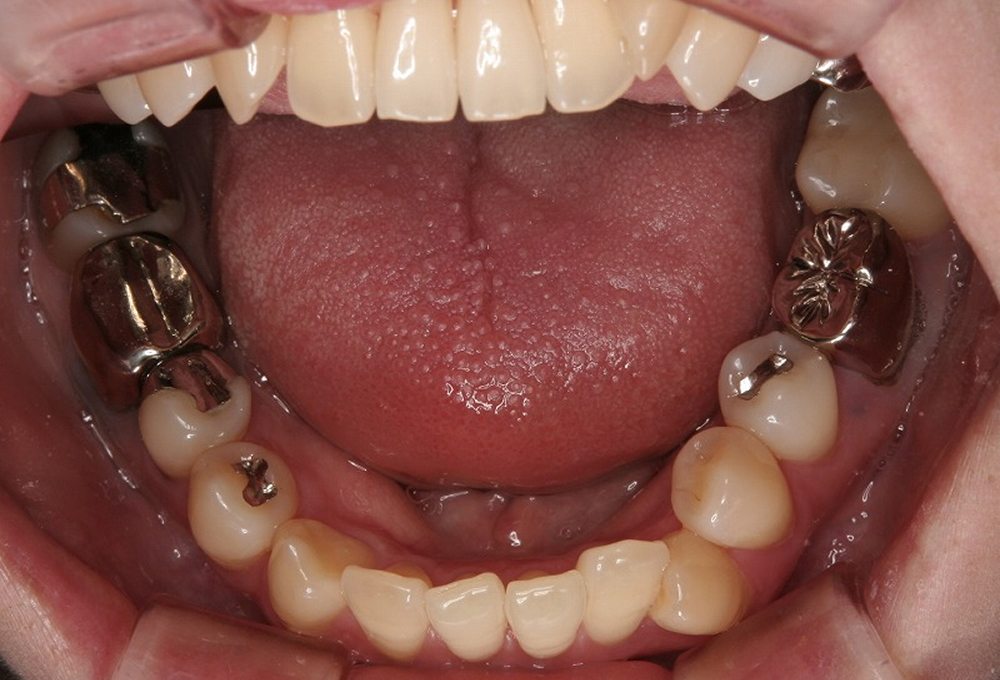

①術前 8歳 下顎4前歯の歯が並ぶスペースが不足。歯列弓も狭少

④1年後スペースが確保され、歯列弓全体も拡大されている。ここまで広がれば,非抜歯で矯正できます